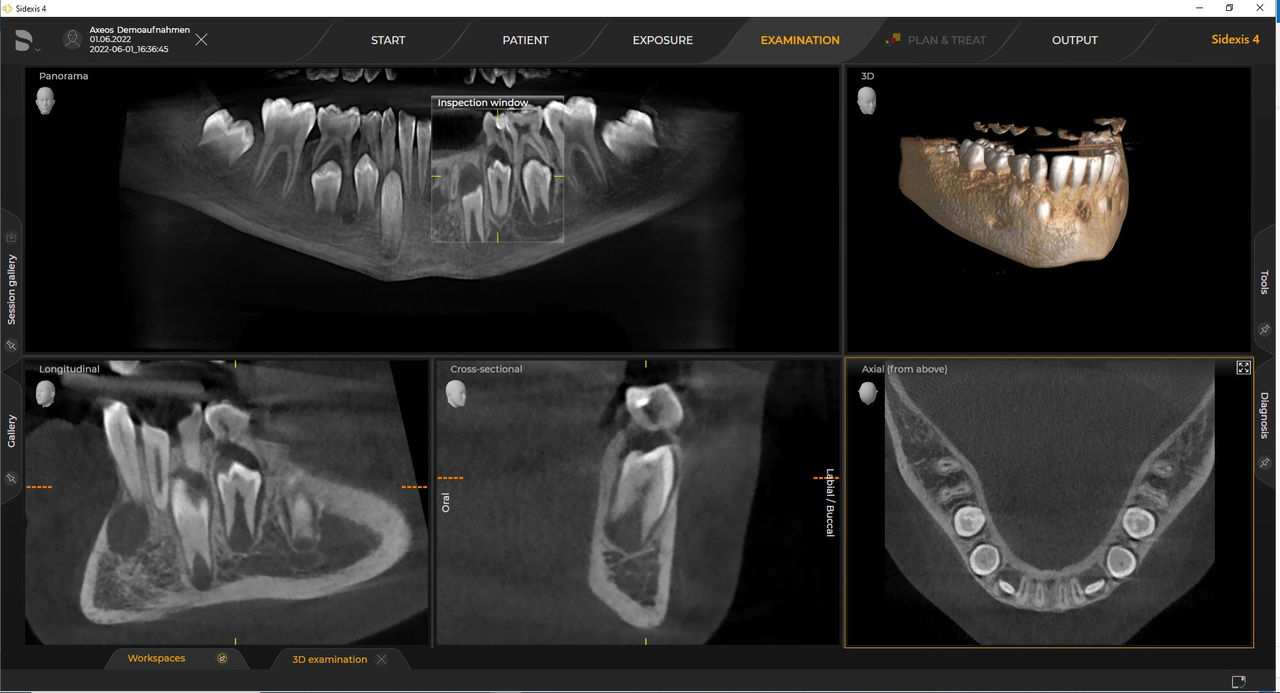

Axeos – the 2D/3D specialist system with a large volume and high image quality for practices with a broad treatment offering. Developed together with dentists and clinicians, Axeos provides the fullest range of functions out of all Dentsply Sirona extraoral X-ray devices. In addition to excellent image quality and tailor-made 3D volume sizes, the dental imaging device is fully optimized for enhanced patient comfort. Axeos not only provides quality in performance and comfort, but also with its award-winning design thanks to the integrated bite block accessory cabinet and ambient light.

Dentsply Sirona 3D units work exclusively with Sidexis 4. Nevertheless data migration from Sidexis XG to Sidexis 4 is very easy. Sidexis 4 allows for the full digital experience with the latest tools.